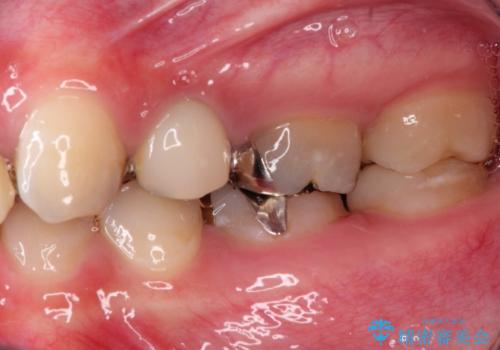

また奥歯にまたがるブリッジも金属のもので、適合もよくありませんでした。

オールセラミックによるやりかえを行いました。